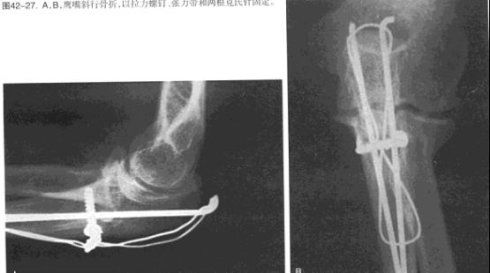

用拉力螺钉做坚强内固定,用接骨板做中和或保护。防止外力作用与骨折所产生的扭矩。弯曲应力和剪切应力,对拉力螺钉起保护作用。穿过接骨板或单独用拉力螺钉对骨片间加压

在中和钢板中,主要受力的为拉力螺钉。当骨折线越大越长时,可以采用2-3枚的拉力螺钉垂直于骨折线进行拉力,再辅助中和钢板固定。中和钢板最常应用于外踝、锁骨等部位的固定。